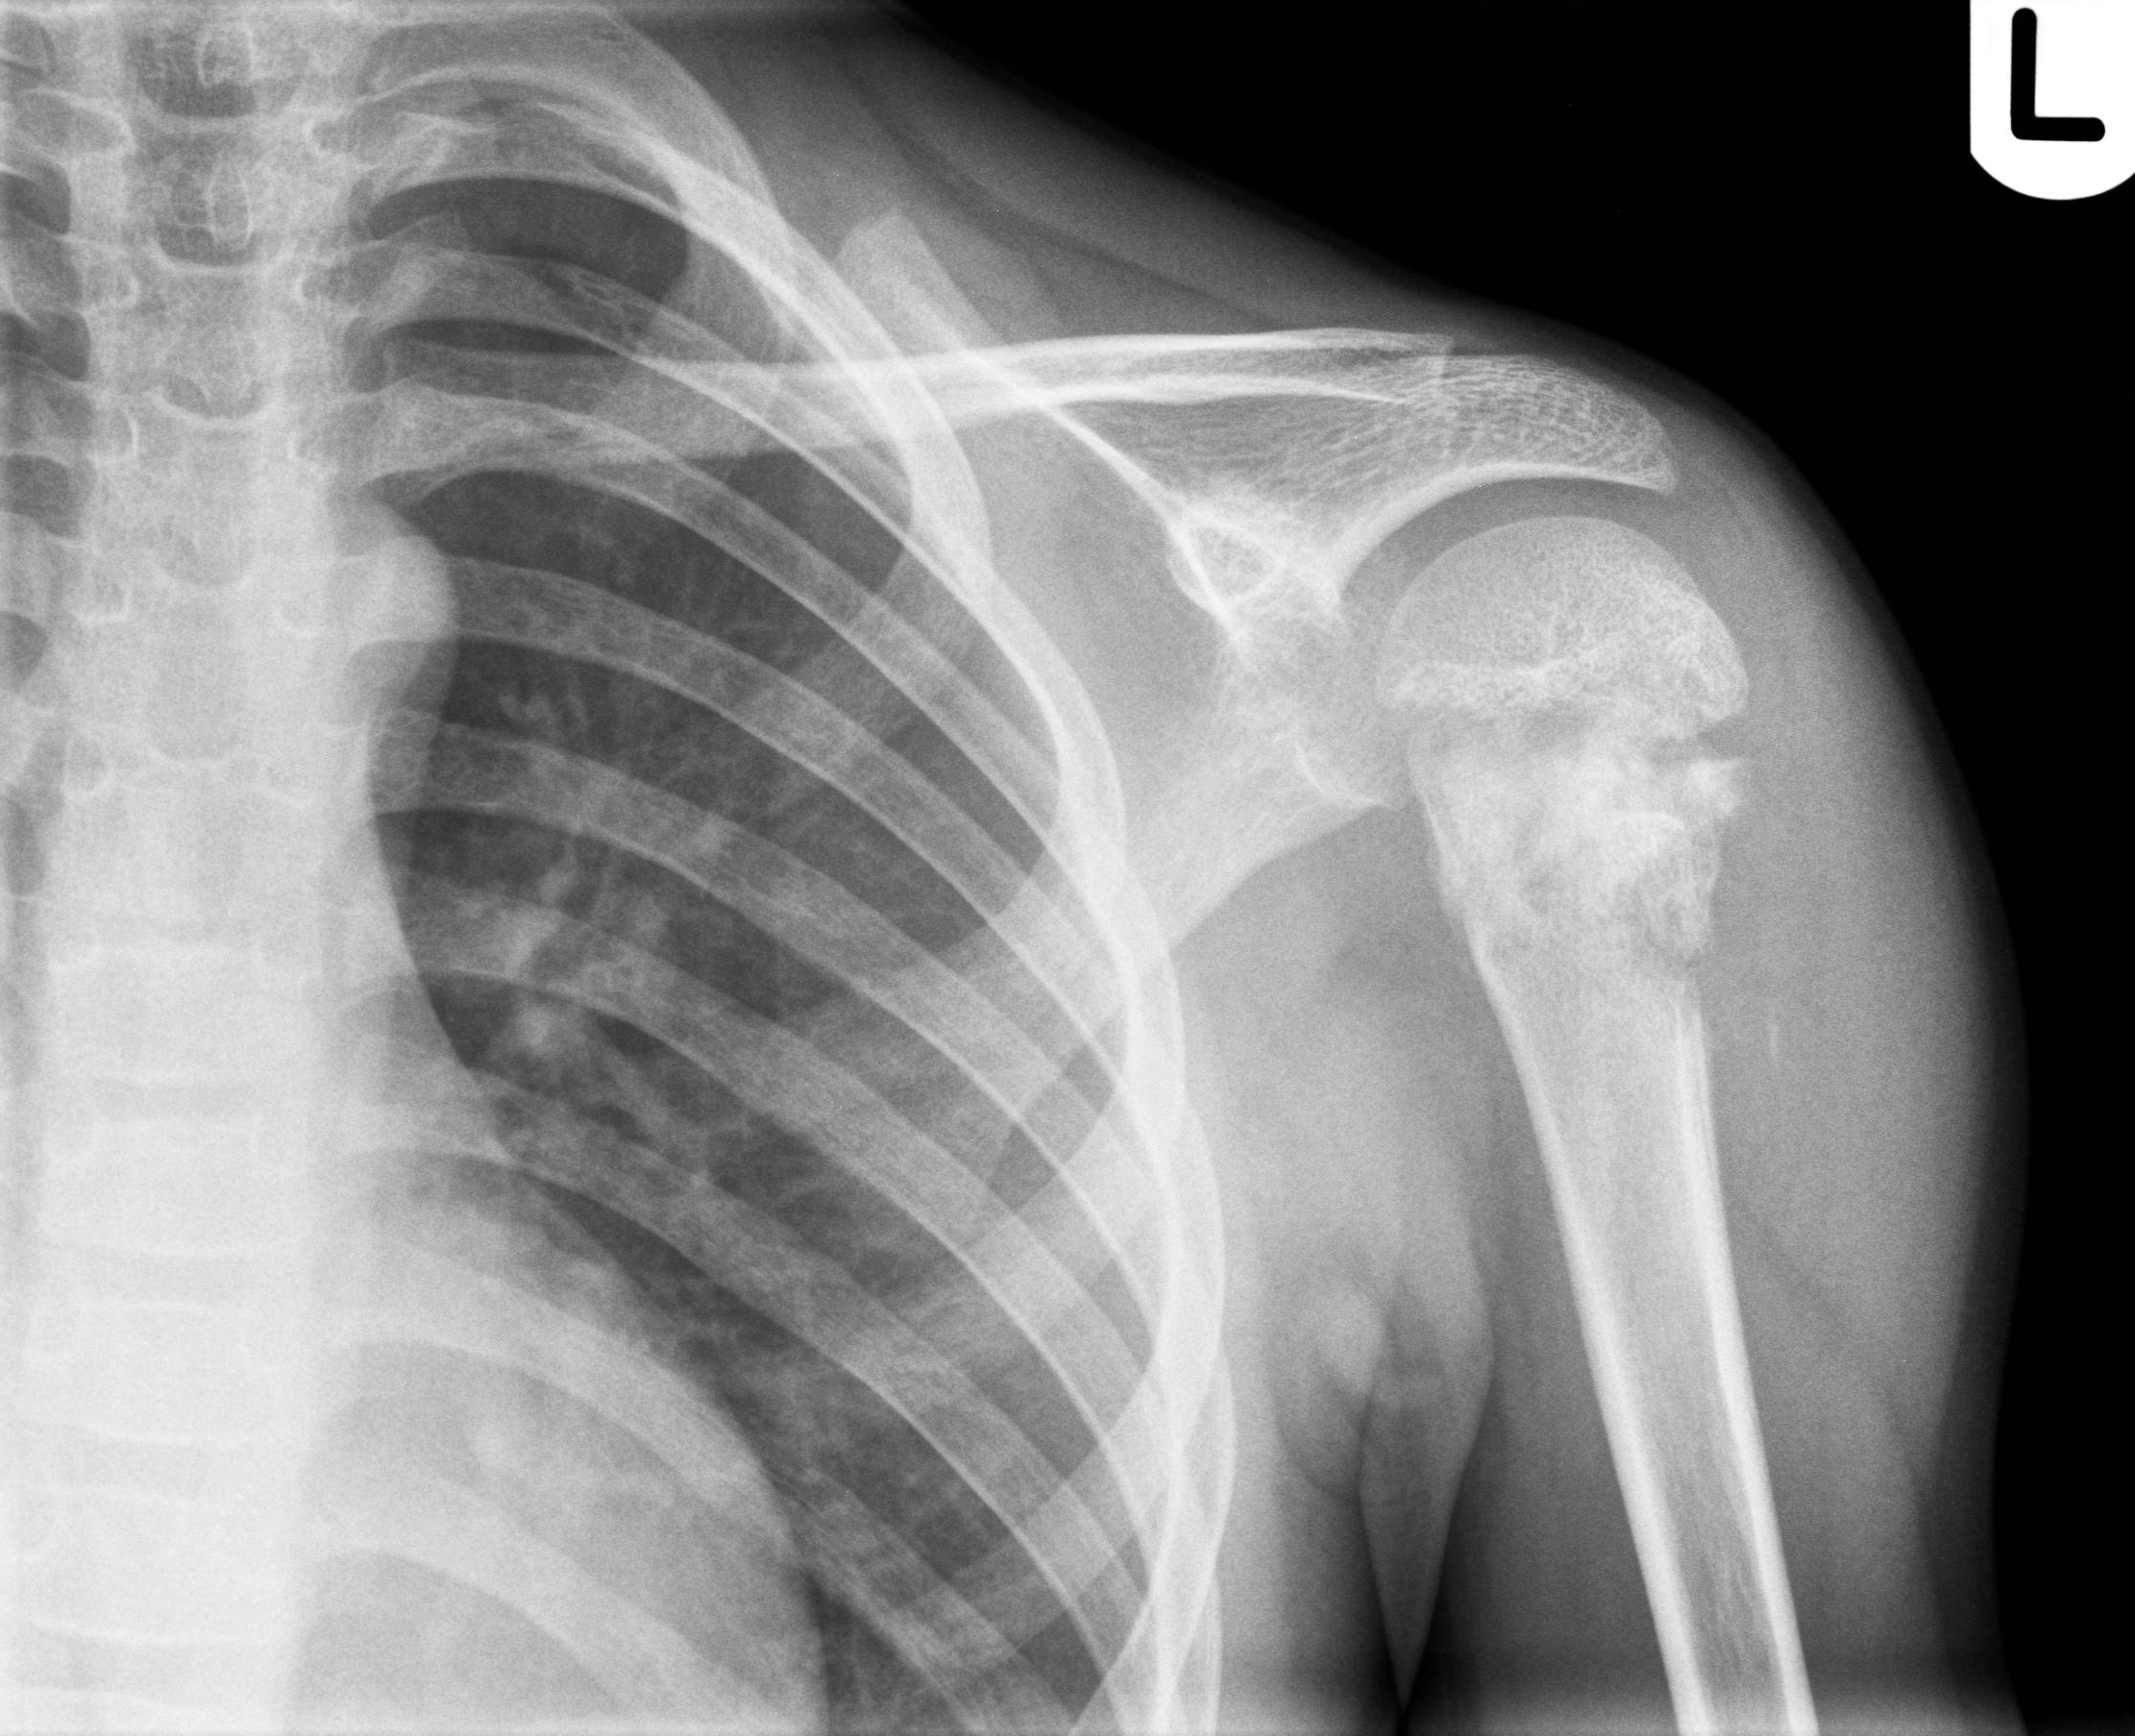

Рентгеновские снимки саркомы плечевого сустава